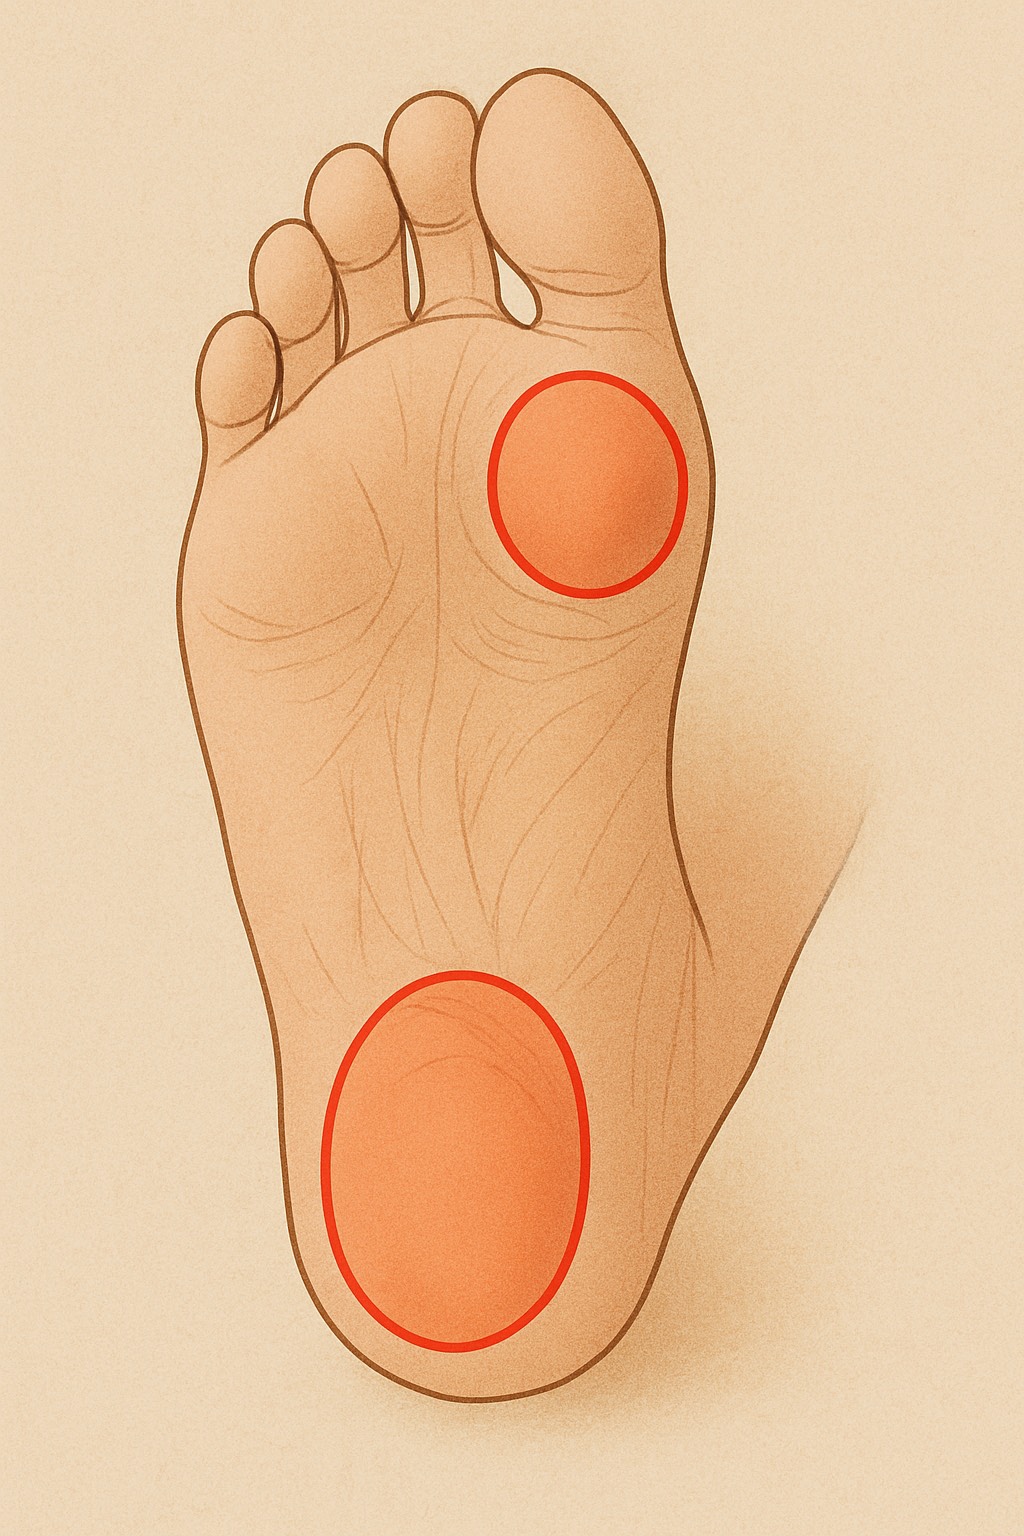

膝のお皿(膝蓋骨)のすぐ下、スネの骨(脛骨)にある

出っ張り部分が強く引っ張られることで炎症が起こり、

膝の下が腫れて痛みを感じます。特に走る・跳ぶ動作を

- 炎症による膝周囲の痛みをやわらげる

- 硬くなった大腿四頭筋やふくらはぎを緩めて、膝への負担を減らす

- 血流を改善し、回復を促す